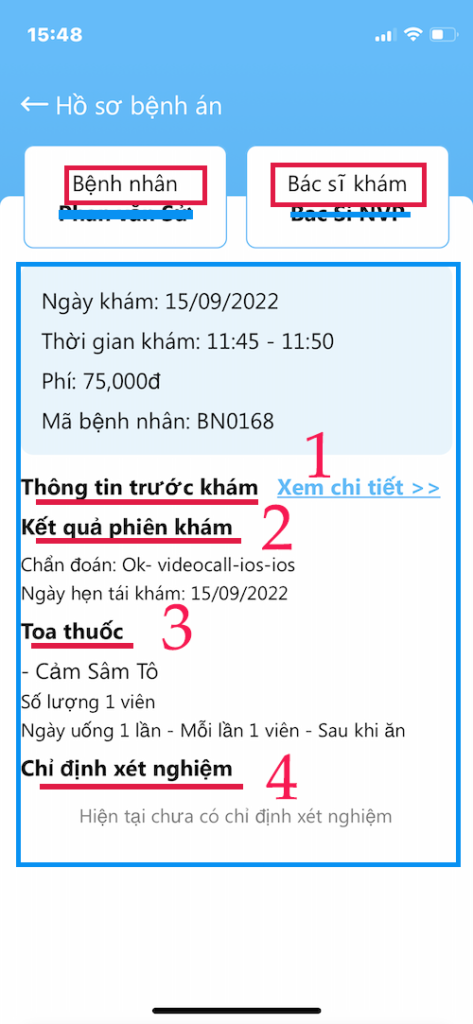

CHI TIẾT BỆNH ÁN

Các thông tin quan trọng của Hồ sơ bệnh án

- (1) Chi tiết trước khám: do bệnh nhân khai

- (2) Kết quả phiên khám: Chẩn đoán, ngày tái khám

- (3) Toa thuốc: thuốc Bác sĩ đã chỉ định

- (4) Chỉ định xét nghiệm: mà Bác sĩ đã cho

XEM CHI TIẾT

Thông tin trước khám

- Các thông tin do bệnh nhân cung cấp

- Các chi tiết khai báo lúc đặt lịch khám

- Lưu ý cung cấp giấy xuất viện, toa thuốc là quan trọng

CHI TIẾT HỒ SƠ BỆNH ÁN

Lấy Toa thuốc từ Bác sĩ

- Hồ sơ bệnh án có thể lấy chi tiết từ nhiều nơi

- Trong hồ sơ bệnh án có Toa thuốc (2)

- Dùng toa thuốc này để mua ở tiệm thuốc tây

- Chẩn đoán bệnh cũng có trong bệnh án